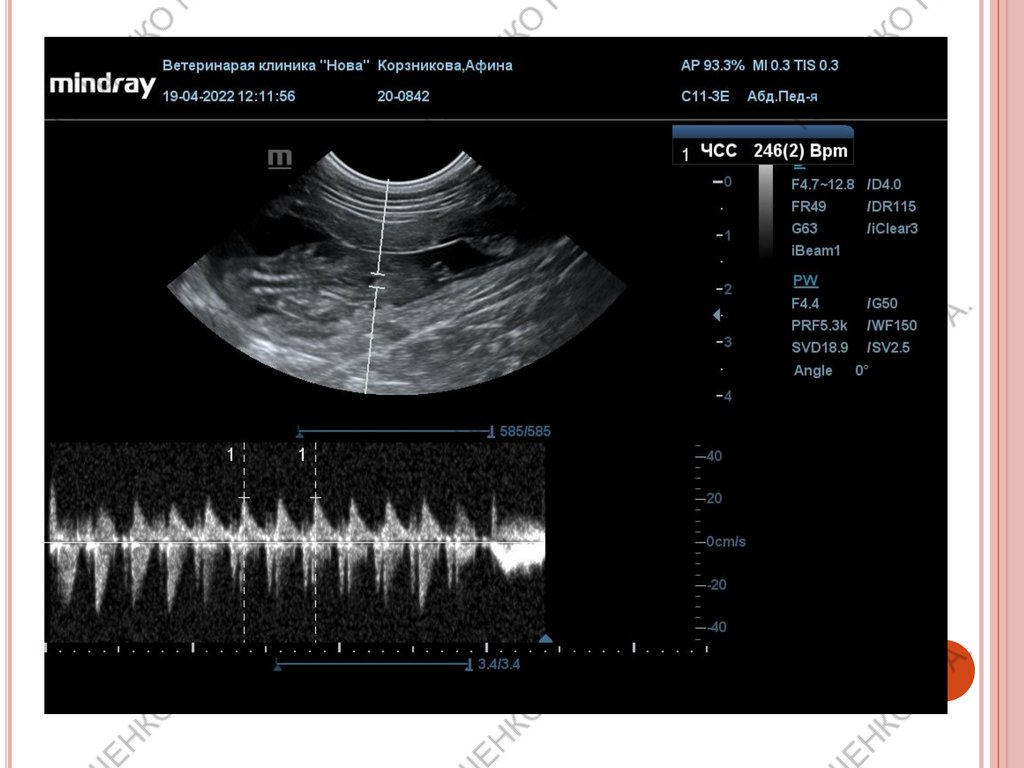

Подсчет ЧСС плодов обязателен на поздних

сроках беременности.

ВАЖНО!

При ЧСС выше 180 уд/мин– норма

ЧСС ниже 180 уд/мин– нужен мониторинг.

ЧСС 160-140 уд/мин – кесарево сечение в

течении 2х часов

ЧСС менее 140 уд/мин – необходимо

экстренное кесарево!